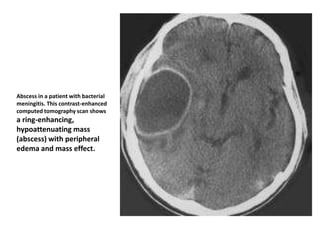

Abscess in a patient with bacterial

meningitis. This contrast-enhanced

computed tomography scan shows

a ring-enhancing,

hypoattenuating mass

(abscess) with peripheral

edema and mass effect.